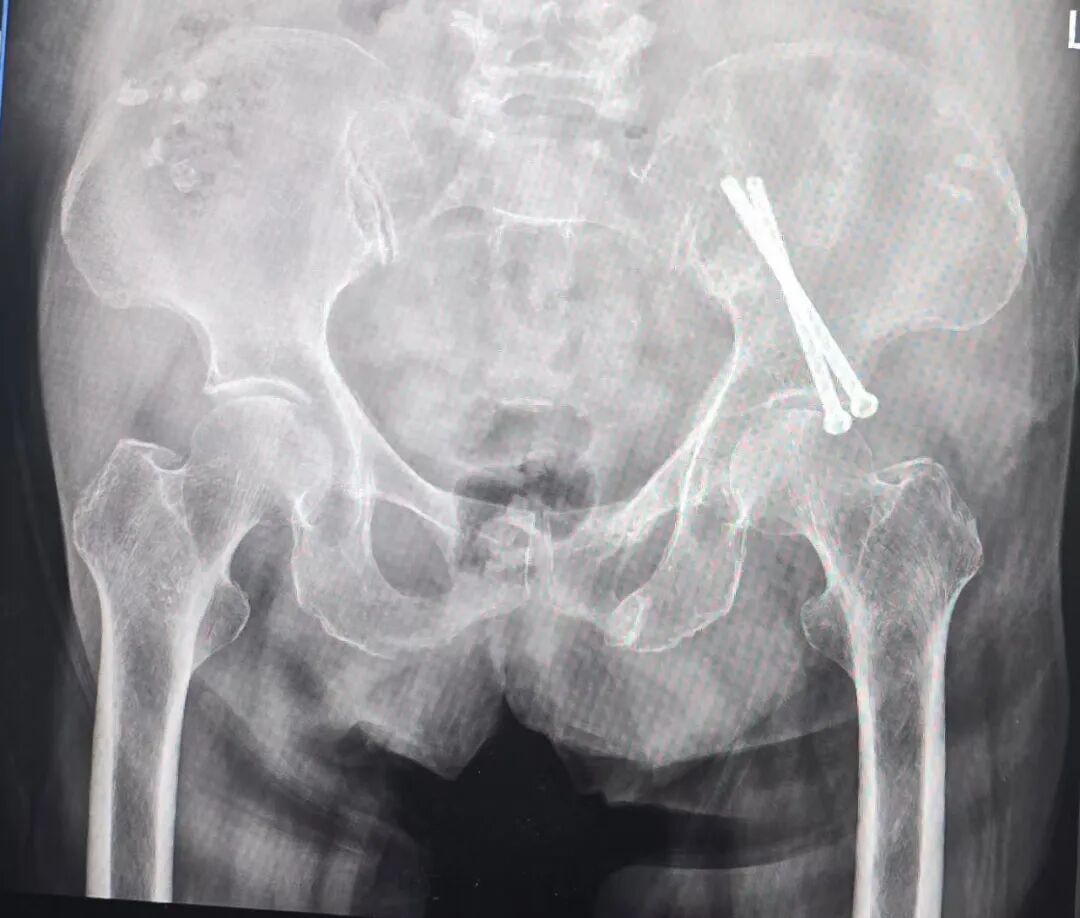

5岁幼童的“精准救治”——贵州省年龄最小的骶髂螺钉固定术成功实施

与高龄患者的手术挑战不同,低龄儿童骨盆发育尚未成熟,骨骼纤细、解剖结构特殊,手术操作需极致精准,避免损伤周围神经血管。骨科三病区接诊的5岁患儿,因外伤导致骨盆骨折,若治疗不当可能影响骨盆发育与未来肢体功能。团队凭借丰富的小儿骨科诊疗经验,创新采用骨盆骨折闭合复位骶髂螺钉内固定技术,在高清影像引导下精准定位骨折端,将细小螺钉微创植入,实现骨折稳定固定。术后患儿恢复迅速,很快恢复正常活动,据公开可查的医疗报道,该案例也成为贵州省年龄最小的骶髂螺钉固定手术成功范例,彰显了团队在小儿复杂骨折治疗中的精湛技艺。

骨盆C型骨折是创伤骨科中极为复杂的骨折类型,骨折移位明显、稳定性极差,治疗难度极大。骨科三病区接诊的一位50多岁患者,遭遇严重外伤导致骨盆C型骨折,若采用传统单一固定方式,难以实现骨折端的稳定复位。团队勇于突破技术瓶颈,创新性采用骨盆骨折闭合复位骶髂螺钉固定 +前环InFix固定技术,通过微创方式同时实现骨盆后环与前环的稳定固定,既保证了骨折复位的精准性,又最大程度保留了骨盆的生理功能。术后患者恢复顺利,各项功能指标逐步正常,该技术的成功应用,填补了安顺地区在复杂骨盆骨折联合微创固定领域的空白,标志着安顺市人民医院骨科在骨盆髋臼手术领域达到省内先进水平。